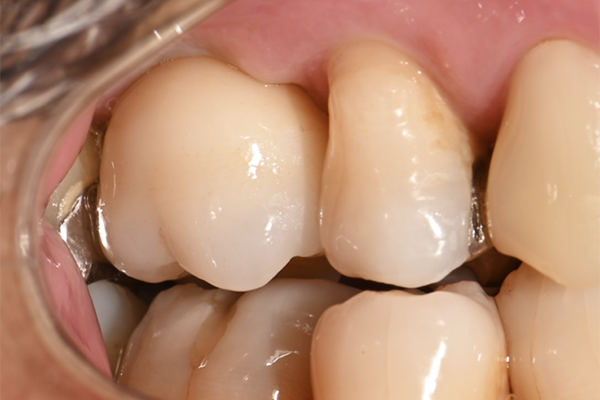

| 主訴 | 右上の奥歯を入れたい |

|---|---|

| 治療内容 | 右上第一大臼歯に対するインプラント治療 |

| 治療期間 | 4ヶ月 |

| 治療費 | 39万5千円 |

| 治療 リスク | インプラントの土台を入れた後最終的な歯が装着されるまで仮歯をしていただきます |